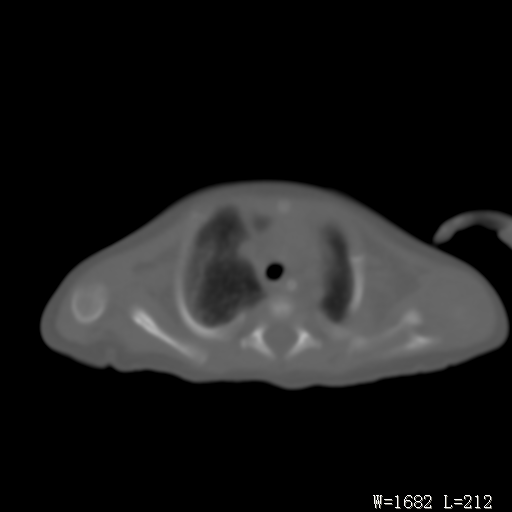

以下是引用改行者在2010-7-8 22:13:00的发言:[br]两肺野透光度降低伴细颗粒状影,两肺下叶见实变影,其内见支气管充气征。 多考虑新生儿肺透明膜病。